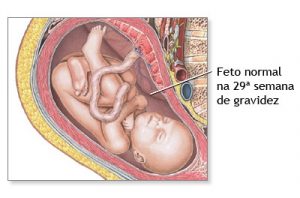

29 Semanas de Gestação

Sua 29a semana começa

- Desenvolvimentoé possível que o bebê dê a cambalhota fisiológica, ficando na posição cefálica (de cabeça para baixo), própria para parto normal.

- Na 29 semana de gravidez, o bebê já começa a se posicionar para o nascimento e é comum sentir ele se virando de cabeça para baixo neste período.

- É uma fase bem ativa para o bebê que se move, vira e brinca o tempo todo dentro da barriga. Faz movimentos tão bruscos que é possível sentir pés, mãos, braços e cotovelos se mexendo.

Com 29 semanas de gestação, o bebê está cada dia mais parecido com aquele que nascerá. Se está à espera de um menininho, essa é a fase em que os testículos descem para o saco definitivamente1. Já nas meninas, o clitóris ainda é proeminente, mas até o nascimento os grandes lábios irão cobri-lo2. Na 29 semana de gravidez, o bebê já começa a se posicionar para o nascimento, e é comum sentir ele virando de cabeça para baixo neste período.

A 29 semana de gravidez é uma fase bem ativa para o bebê que se move, vira e brinca o tempo todo dentro da barriga. Faz movimentos tão bruscos que é possível sentir seus pés, mãos, braços e cotovelos, inclusive, causando certo incômodo para a mamãe. O bebê chega a medir nesta semana algo em torno de 38,6 cm e pesar cerca de 1,153 kg. Já está bem grandinho, não?

Seus órgãos, assim como cada sentido do seu corpo, está se desenvolvendo e fica cada vez mais maduro para sobreviver após o nascimento. Com 29 semanas de gestação, a função do pulmão começa a ficar ativa e ele vai aprendendo a controlar a respiração. Além disso, seu corpo já consegue manter sozinho uma temperatura adequada.